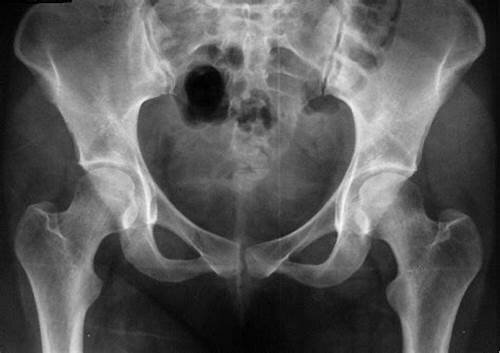

• Enfermedad de Legg-Calvé-Perthes

Enfermedad de Legg-Calvé-Perthes

Arthur T. Legg, Jacques Calvé, Georg Perthes. Es una afección ortopédica infantil que repercute en el desarrollo de la cadera.